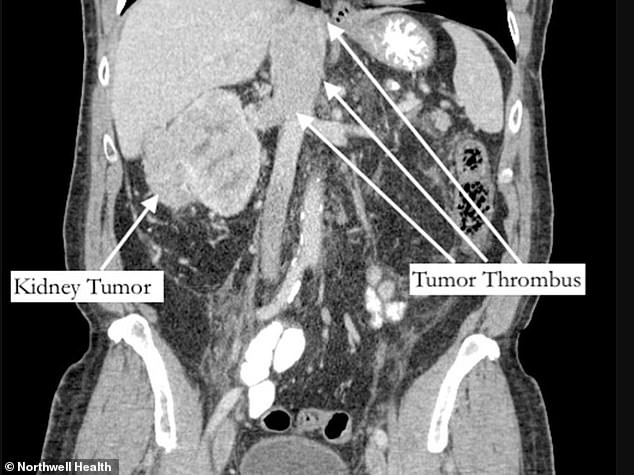

Diese zeigten einen 2,5 Pfund schweren Nierentumor auf der rechten Seite seines Unterleibs, der auch fußlange Verlängerungen – medizinisch Tumorthrombus genannt – hatte, die zwei Hauptarterien teilweise blockierten.

Dies ist ein Scan von Bernstein. Es zeigt den Nierentumor auf seiner rechten Seite, wobei auch der fußlange Tumorthrombus in den Venen zu sehen ist